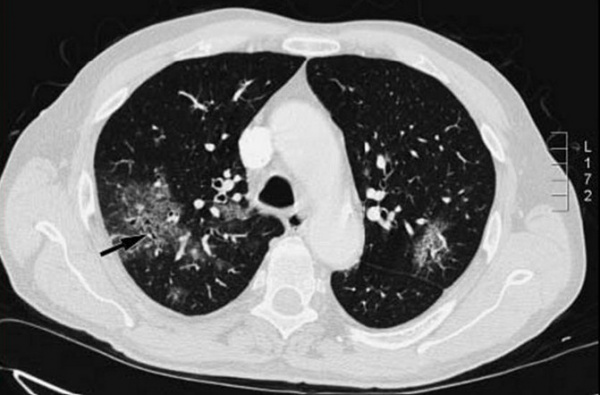

Часто подобные инфильтративные изменения в легких удается выявить только при компьютерной томографии. Возможно атипичное проявление пневмонии (не является редкостью у иммунокомпрометированных больных) в виде локальной, очаговой инфильтрации, присутствия полостей. Появление жидкости в плевральных полостях не специфично для пневмоцистной пневмонии и определяется крайне редко при моноинфекции.

На рентгенограммах и КТ легких в типичных случаях определяется облаковидное понижение прозрачности легочных полей, получившее название «хлопьев снега» или «ватного легкого». Иногда рентгенологические изменения отсутствуют или имеют атипичную картину. С помощью ФВД обнаруживаются признаки дыхательной недостаточности по рестриктивному типу; исследование газового состава крови свидетельствует о гипоксемии.

- Рентгенологические. В начальной стадии пневмоцистной пневмонии на рентгенограммах легких выявляются инфильтраты, похожие на очертания крыльев бабочки. В разгаре инфекции заметны двусторонние симметричные очаги уплотнения, чередующиеся с участками вздутия («ватное» легкое). На КТ грудной клетки обнаруживаются участки инфильтрации по типу «матового стекла».